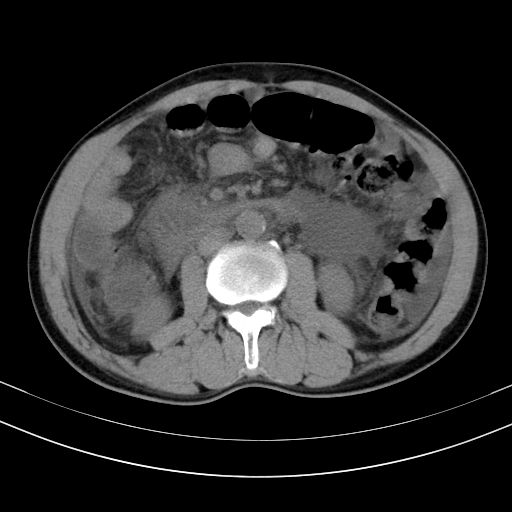

以下是引用随光逐影在2010-2-28 10:23:00的发言:[br]1)考虑肝癌;建议行ct增强扫描检查。2)肝硬化,脾大,腹水。3)慢性胆囊炎。

以下是引用dyqct在2010-2-28 16:44:00的发言:[br][quote]以下是引用随光逐影在2010-2-28 10:23:00的发言:[br]1)考虑肝癌;建议行ct增强扫描检查。2)肝硬化,脾大,腹水。3)慢性胆囊炎。